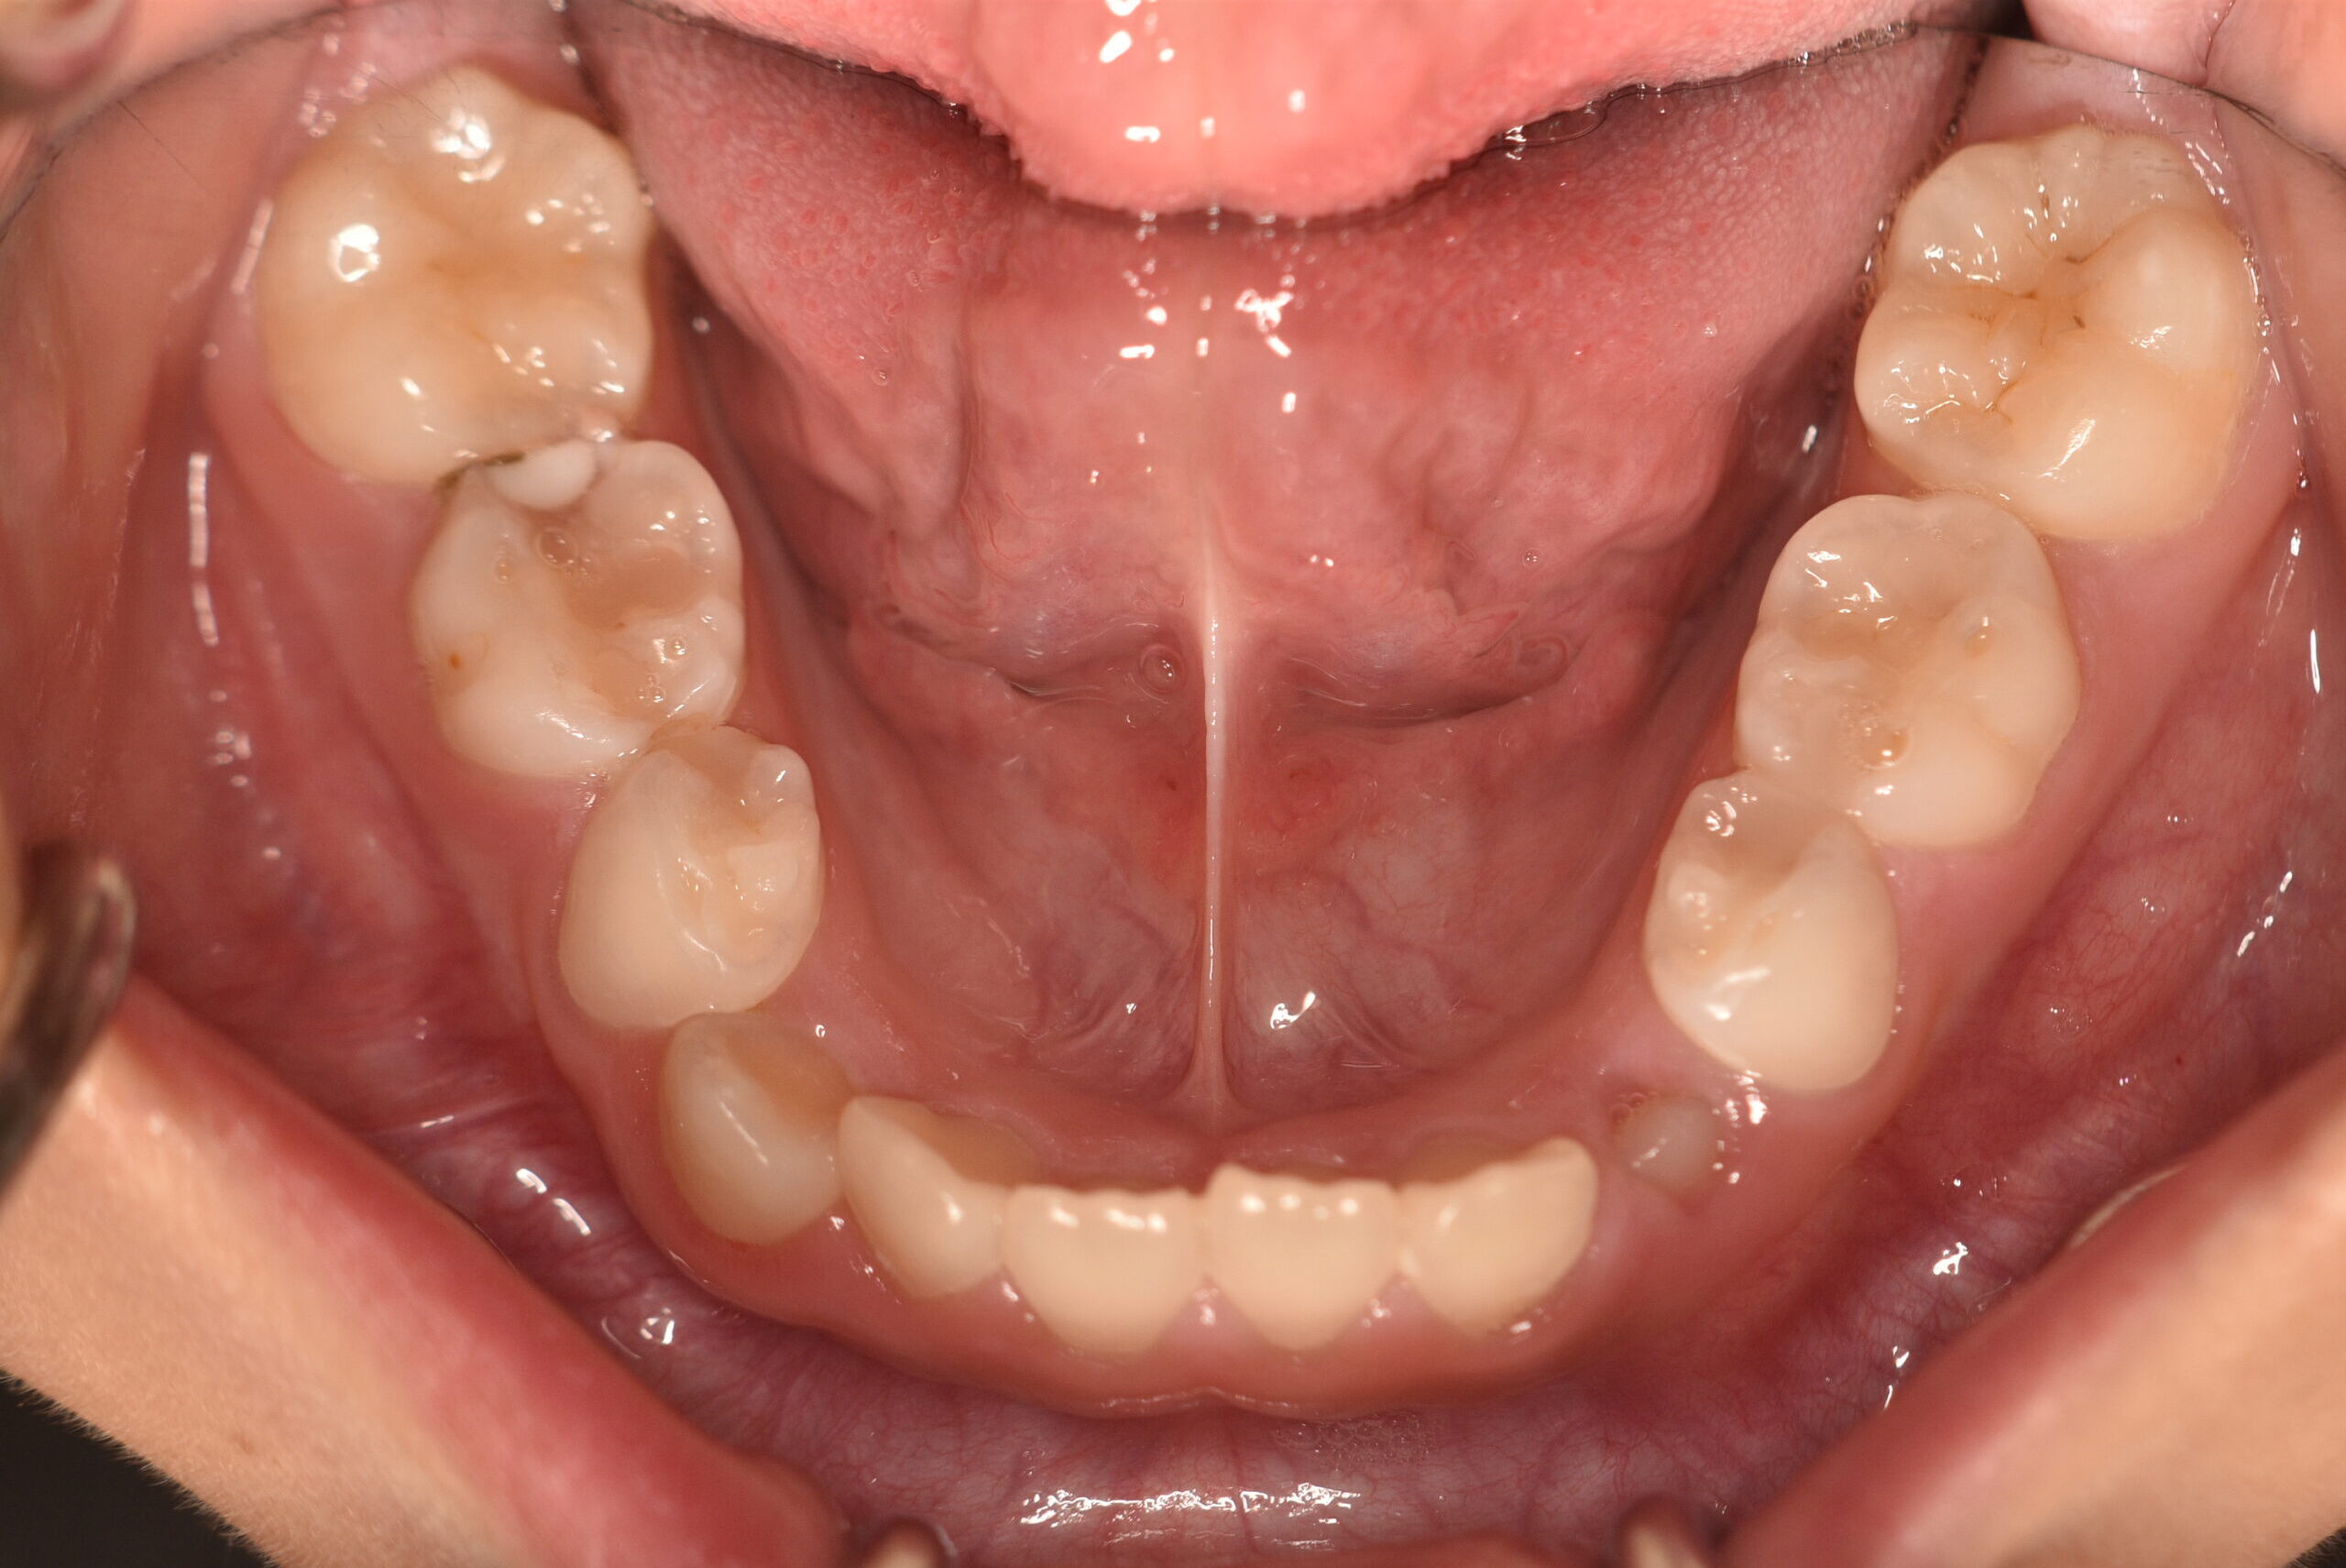

| 初診時 年齢 |

8歳8ヶ月 | 性 別 | 女性 |

|---|---|---|---|

| 治療期間 | 4年3ヶ月 | 費 用 | 矯正施術料:800,000円 調整料:4,000円/月 |

| 治療内容の詳細 | 初診時8歳の女性で、下顎が出ていると歯科医からの指摘を気にされ来院されました。 検査の結果、反対咬合を伴うアングルⅢ級不正咬合と診断しました。 治療としては、初期段階の治療として、リンガルアーチを使用して上顎前歯部を前方へ移動させ、反対咬合の改善を行いました。また、機能的矯正装置で鼻呼吸の獲得と舌の位置や口唇の閉鎖といった筋機能習癖の改善を行いました。 永久歯列に交換後、非抜歯の上、セルフライゲーションブラケット装置(デーモンシステム)で歯の配列を行いました。 治療期間は、4年3ヶ月でした。 |